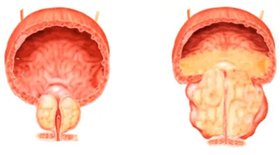

Интерес авторов к проблеме лечения ДГПЖ был вызван ростом распространенности этой патологии среди мужчин старшего и пожилого возраста, значительным снижением качества жизни и развитием сексуальных нарушений, связанных не только с симптомами болезни, но и с побочным действием медикаментозной терапии. Известно, что с увеличением продолжительности жизни заболеваемость ДГПЖ постоянно возрастает: гистологические признаки выявляются у 60 % мужчин в возрасте старше 50 лет, а после 70 лет их частота увеличивается до 80 %. Ежегодные расходы на лечение ДГПЖ на мировом рынке превышают 4 млрд долларов.

ДГПЖ является хроническим прогрессирующим полиэтиологическим заболеванием, связанным с повышением активности тестостерона и дигидротестостерона — андрогенов, стимулирующих процессы роста и дифференциации тканей предстательной железы. Ключевая роль в развитии гиперплазии простаты принадлежит более активному дигидротестостерону, образующемуся из тестостерона при помощи фермента 5α-редуктазы (5АР) с участием кофермента НАДФ-Н. Основой медикаментозной терапии ДГПЖ являются блокаторы α-адренорецепторов (альфузозин, тамсулозин) и ингибиторы 5α-редуктазы (финастерид). Альтернативу синтетическим лекарствам составляют фитопрепараты, зарекомендовавшие себя как эффективные и безопасные средства терапии ДГПЖ, в частности экстракт Serenoa repens.